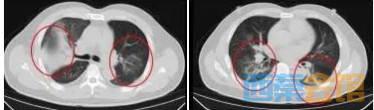

感染科医疗团队充分注意到顾先生“刚从国外归来”的特殊情况,并结合非洲当地的流行病学背景,高度怀疑其可能感染了某种特殊病原体。医疗团队为顾先生安排了支气管镜检查,并通过灌洗液的基因检测技术,最终锁定了致病元凶——贝纳柯克斯体,即“Q热”

在感染科医护团队的精心治疗与细致护理下,顾先生的发热、咳嗽、胸闷等症状逐渐缓解。复查的CT结果显示,肺部炎症情况得到了明显的改善。目前,顾先生已经顺利康复出院。